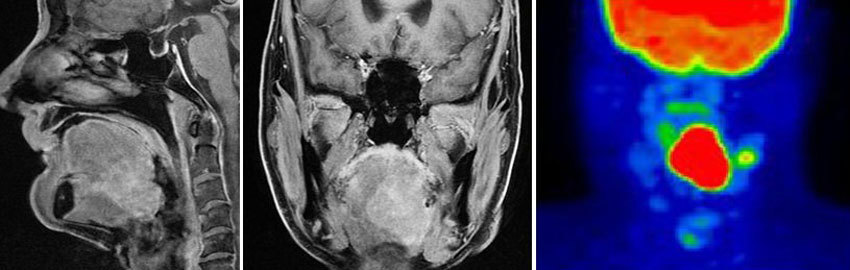

Магнитно-резонансная томография.

Позитронно-эмиссионная томография (ПЭТ-сканирование) — одно из самых информативных исследований, которое помогает обнаруживать отдаленные метастазы. Во время процедуры в организм пациента вводят радиофармпрепарат — специальное слабое радиоактивное соединение, которое накапливается в раковых клетках.

Затем делают снимки с помощью ПЭТ-томографа, и на них хорошо видны все опухолевые очаги. Для большей информативности ПЭТ выполняют параллельно с компьютерной томографией и совмещают снимки — такое исследование называется ПЭТ-КТ.